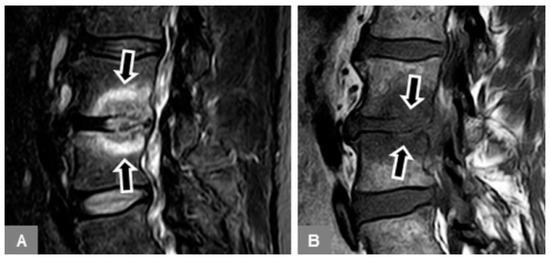

3.5. Appearance of the Intervertebral Disc